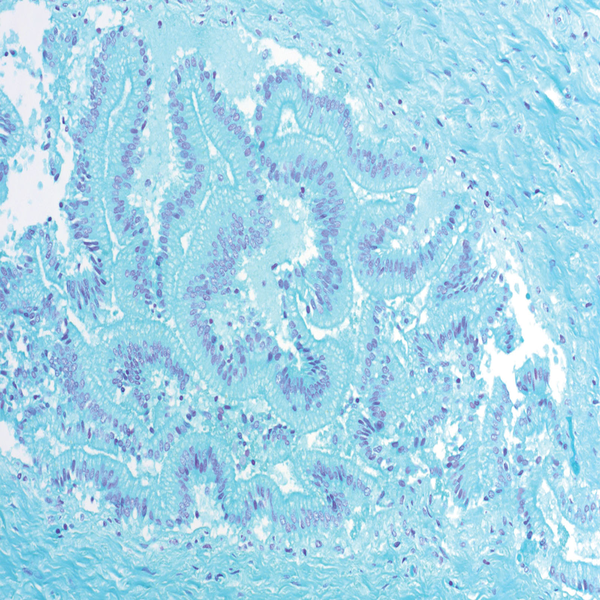

- General and specialized tissue and cell staining

Histological methods includes sample processing in the pathology laboratory, preparation of the slide and its examination under a microscope, sample fixation, molding, microtome cutting, staining and assembly of the slides.